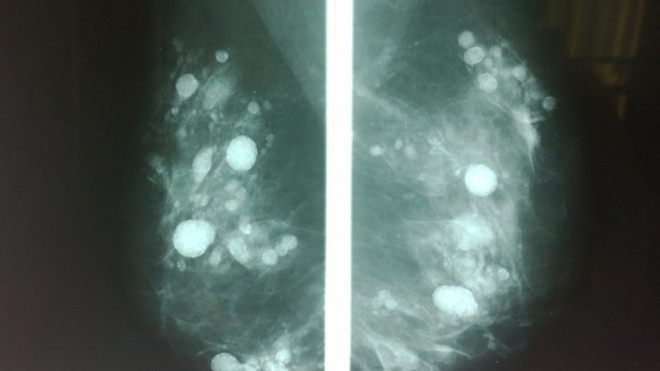

Hàng trăm 'đốm sáng' vì silicon khiến chuyên gia không thể phát hiện khối u (nếu có).

Trước khi quyết định phẫu thuật, nữ bệnh nhân này đến Khoa Ung bướu-Ngoại tổng quát khám vì cảm thấy "đau và lợn cợn tại vú kéo dài". Sau khi khai thác bệnh sử và tiến hành X-Quang tuyến vú, hình ảnh khiến các chuyên gia bối rối bởi không thể phân biệt được đâu là khối u (nếu có), còn đâu là silicon.

"Silicon lỏng có rất nhiều tác dụng phụ như gây loét kéo dài, đau, co rút biến dạng, tạo cục hoặc di chuyển vô phổi, thận…Đặc biệt tại khi tiêm vào vú, sau thời gian silicon kết thành khối gây nhiều nốt trong vú, rất khó phân biệt với khối u, do đó nếu bệnh nhân chẳng may bị ung thư sẽ khó phát hiện sớm", BS Vũ cho biết.